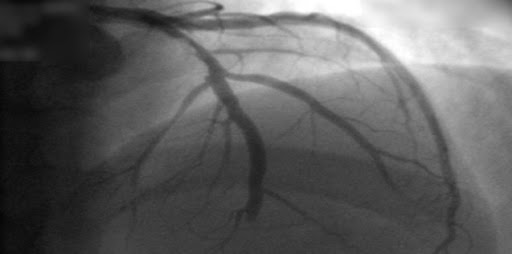

En pacientes con infarto de miocardio con elevación del segmento ST sometidos a revascularización percutánea completa, una estrategia guiada por la rserva fraccional de flujo no tuvo un beneficio significativo sobre una estrategia guiada por angiografía, si bien los intervalos de confianza para la estimación del efecto fueron amplios. New England Journal of Medicine, 22 de julio de 2021.

Enfermedad coronaria estable: ¿estrategia conservadora o invasiva?

Dos artículos describen los hallazgos de un gran  estudio aleatorizado, que no muestra ventaja en sobrevida o en eventos isquémicos para la estrategia invasiva, pero sí cierta reducción en los síntomas anginosos. New England Journal of Medicine, 30 de marzo de 2020.

¿Revascularización completa o sólo de la lesión culpable?

En pacientes con infarto de miocardio y enfermedad coronaria multivaso, la revascularización completa fue superior al tratamiento limitado a la lesión culpable. New England Journal of Medicine, 1° de septiembre de 2019